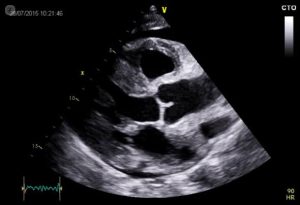

Dr. Armughan Riaz - Heart Specialist Sialkot